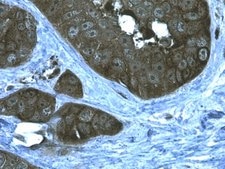

Immunohistochemistry Analysis: 1:100 dilution from a previous lot detected Heat Shock Protein 90α in human prostate adenocarcinoma tissue.